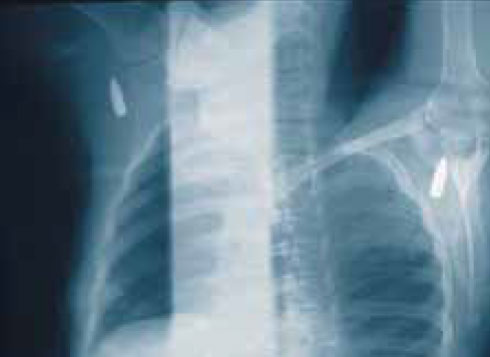

Рисунок 6. Перелом плечевой кости, пуля остановилась в подлопаточной мышце

Рисунок 7. Пуля, расположенная экстрасиновиально вблизи бедренной кости